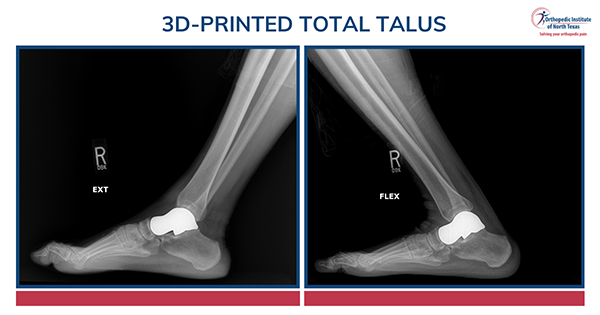

What additive technology allows us to do in foot and ankle surgery is create highly specific, patient-matched solutions to highly specific structural problems. In the case of a 3D-printed total talus, we can use advanced imaging and CAD modeling to design an implant that closely reproduces the patient's anatomy. We can restore shape, preserve limb length, correct deformity, and replicate the relationship between the ankle and hindfoot far more faithfully than traditional salvage procedures ever could.

That is why this is so compelling. Historically, many salvage procedures required us to sacrifice anatomy in order to save the limb. A patient-specific total talus does not do that in the same way. It is designed to preserve motion, preserve length, and allow the foot and ankle to move in a way that more closely mirrors how that person's anatomy was intended to function.

For a straightforward isolated total talus, patients are often walking in a cast by one week after surgery, and many are in a shoe by around six weeks. Again, that is not a promise. It is a general framework. But it is an important one, because many of the alternative operations in this space are more morbid and more disabling.

What patients tend to value most is simple: standing no longer hurts the same way, and motion is preserved.

Range of motion is often maintained at least to the level patients had before surgery, but now the arc of motion is much less painful. I love the first postoperative visit for exactly this reason. When I gently range a patient's ankle and watch their expression change from nervous anticipation to visible relief, that is one of the most gratifying moments in practice. You can see them realize, in real time, that moving the ankle no longer brings the same pain.